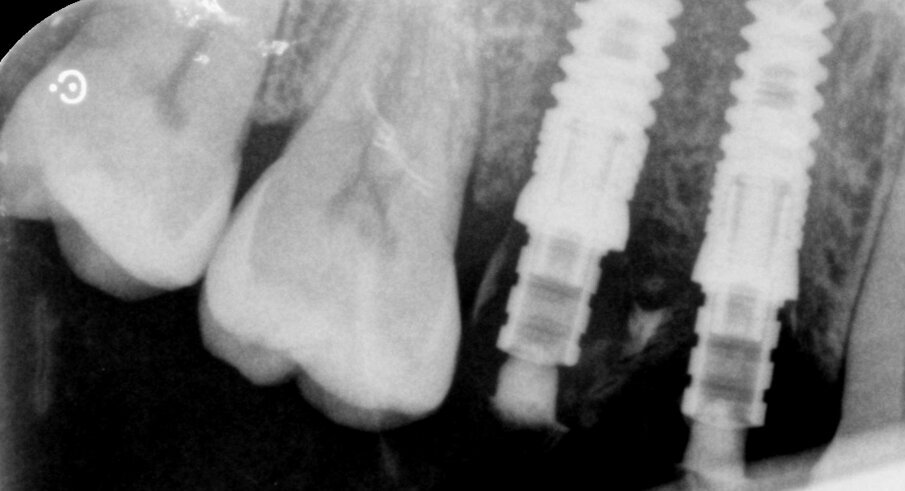

Fig. 1_Radiografia periapicale a 8 settimane dall’estrazione di 14 e 15.

Fig. 7_Rx post-operatoria.

Fig. 12-14_Corone definitive e rx di controllo a due anni dalla chirurgia.